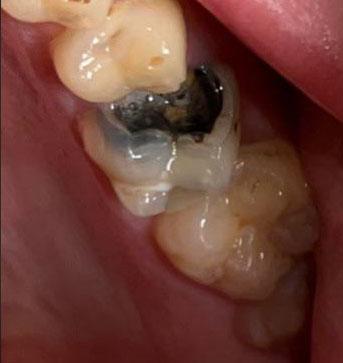

The image shows a posterior molar tooth with an old metallic (amalgam) filling. The restoration appears damaged with visible breakdown at the margins. There are signs suggesting possible secondary decay beneath or around the filling.

Large amalgam (silver) filling on molar

Marginal gap between filling and natural tooth

Dark discoloration around restoration edges

Possible enamel fracture near filling

Plaque retention around restoration

Surrounding gum tissue appears mildly irritated

Adjacent teeth appear intact